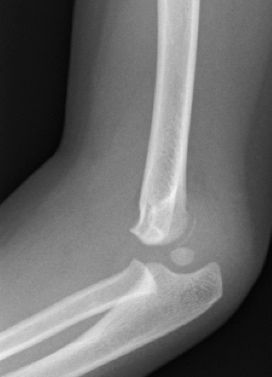

Figura 8: a-d, Imagen radiografica de fractura del cóndilo lateral con desplazamiento articular. Tratamiento quirúrgico mediante reducción abierta y osteosíntesis.